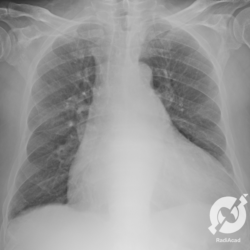

Aumento do volume cardíaco, inversão da circulação pulmonar, lesões intersticiais reticulares e obliteração do seio costofrênico direito.